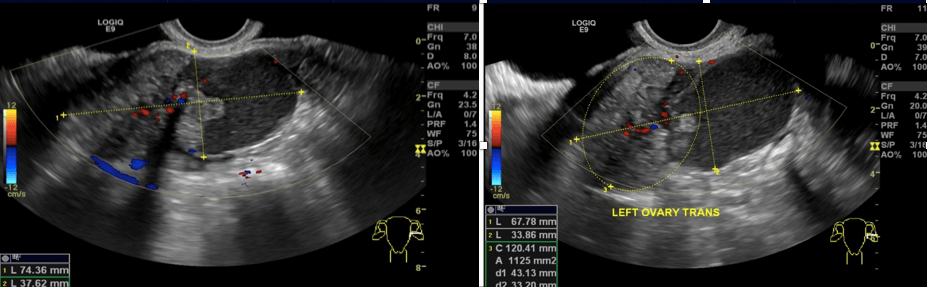

Resim 1: Transvajinal ultrason ile saptanan sol yumurtalık tümörü